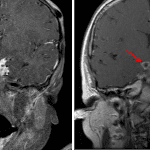

Findings

- Nodular enhancing soft tissue filling the suprasellar cistern and extending into the cavernous sinus, interpeduncular fossa, anterior interhemispheric fissure, and right greater than left ambient cisterns and sylvian fissures with areas of internal T2 signal hypointensity

- Peripherally enhancing components contiguously extend into the parenchyma of the inferior right frontal lobe, hypothalamus, and medial right temporal lobe with surrounding T2/FLAIR signal hyperintensity throughout a larger area of the right greater than left inferior frontal lobes, right temporal lobe, right greater than left basal ganglia and thalami, and right greater than left midbrain

- Small area of restricted diffusion in the approximate location of the anterior commissure on the right

- Mild generalized cerebral edema with FLAIR signal hyperintensity in multiple cerebral sulci and otherwise mild multifocal leptomeningeal enhancement

- Abnormal enhancement about the communicating segments of the right greater than left internal carotid arteries, M1 segment of the right MCA, right posterior communicating artery, P1 segment of the right PCA, and distal basilar artery with asymmetric narrowing of the communicating segment of the right ICA

Diagnosis

- Tuberculous meningitis

Extensive basal meningitis with differential considerations including tuberculosis as well as other bacterial and fungal pathogens. Recommend CSF sampling for further evaluation.

Peripherally enhancing components contiguously extend into the parenchyma of the inferior right frontal lobe, hypothalamus, and medial right temporal lobe concerning for small abscesses with surrounding larger areas of cerebritis.

Findings concerning for vasculitis involving the right greater than left internal carotid arteries, M1 segment of the right MCA, right posterior communicating artery, P1 segment of the right PCA, and distal basilar artery with asymmetric narrowing of the communicating segment of the right ICA. A small area of restricted diffusion in the approximate location of the anterior commissure on the right could represent a small perforator infarct vs infectious debris. No additional evidence for an acute infarct.